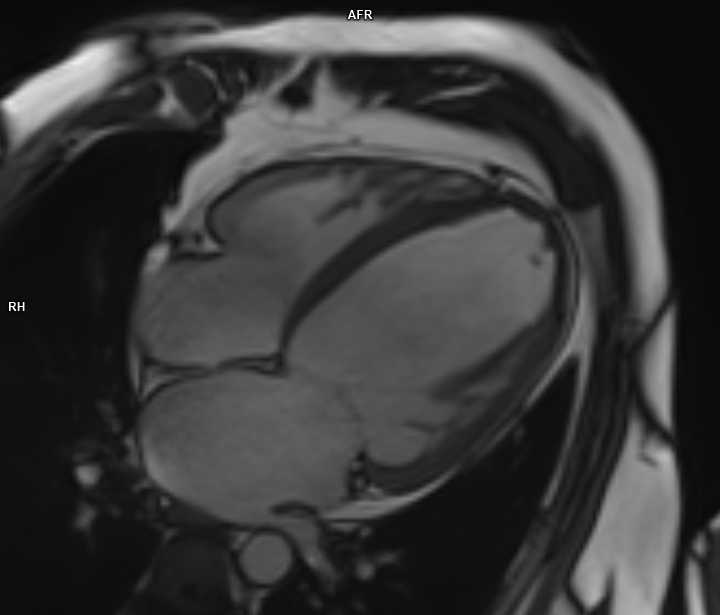

Na začátku roku 2018 referován ošetřujícím internistou na naše pracoviště ke koronarografii pro oprese na hrudi a výraznou námahovou dušnost s epizodami dušnosti noční při nově zjištěné těžké systolické dysfunkci LKS. Na EKG sinusový rytmus s TF 110/min, QRS komplex 100 ms, iLBBB. Koronarografie provedena v ambulantním režimu nekomplikovaně transradiálním přístupem s nálezem jemných nerovností na věnčitých tepnách, ischemická etiologie srdečního selhání vyloučena. Při doplněné levostranné ventrikulografii potvrzena těžká systolická dysfunkce s EF LKS 25 %. Upravena farmakoterapie srdečního selhání – ponechána léčba perindoprilem (5 mg 1× denně), nově zahájena léčba beta-blokátorem (bisoprolol 5 mg 1× denně), spironolaktonem (25 mg 1× denně) a furosemidem (20 mg 1× denně). Otec pacienta zemřel v 68 letech na srdeční selhání při dilatační kardiomyopatii (DKMP), na doplněné magnetické rezonanci srdce u pacienta rovněž popsán obraz DMP s těžkou dysfunkcí LKS.

Obr. 2. Magnetická rezonance srdce